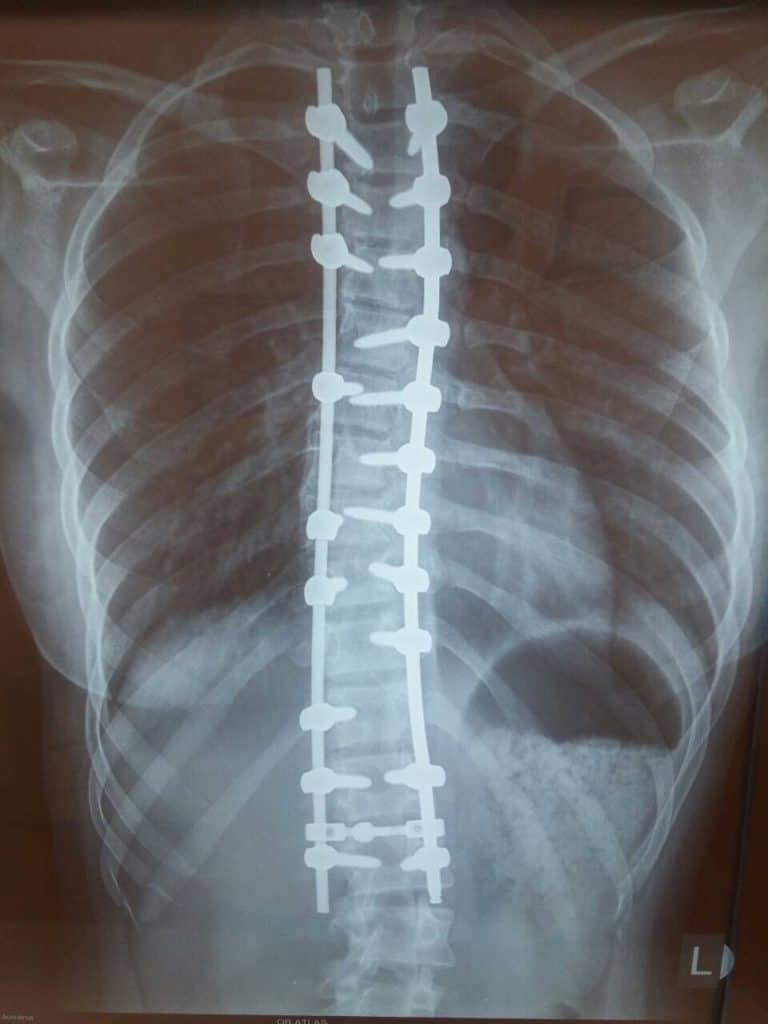

Medicinski tim ortopedskih hirurga i neurohirurga (spinalnih hirurga) Atlas opšte bolnice je po prvi put u Srbiji izveo kompletnu endoskopsku operaciju korekcije deformiteta kičme što je trenutno najsavremeniji vid operativnog lečenja u svetu.